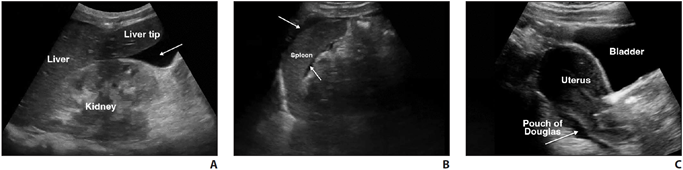

Evaluating intraperitoneal free fluid in the setting of trauma is among the most well-established uses of POCUS. First described in Europe in the 1970s and adopted in the United States by the 1990s, this examination is now known as “focused assessment with sonography in trauma” (FAST) [12]. The FAST examination includes a quick survey of key areas in the intraperitoneal cavity for free fluid, a sign of hemorrhage, and an indirect indication of organ injury; cardiac and thoracic components are also included. The abdominal component of FAST evaluates the right and left upper quadrants, focusing on the perihepatic and perisplenic spaces, respectively, along with the pelvis [11, 12] (Fig. 1).

The amount of free fluid detected at a specific point in time depends on the rate of accumulation, location, and the patient’s position [9]. Free fluid gravitates to the most dependent area, which is the right upper quadrant (RUQ) in a supine patient [16]. Within the RUQ, the hepatorenal recess (also known as Morison pouch) is a common area of interest; however, the caudal tip of the liver is where fluid tends to collect first. In the left upper quadrant, attention should be directed to the perisplenic area, particularly in the subdiaphragmatic space. In the pelvis, fluid tends to collect posterior to the uterus, known as the pouch of Douglas, in females and in the rectovesicular space or lateral to the bladder in males [17] (Fig. 2).